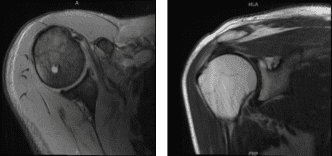

The patient presented MRI results that showed rotator cuff tendinosis most pronounced at supraspinatus tendon where a full-thickness tear at the central aspect of the insertion measures 8 mm and there is low-grade partial-thickness articular sided tearing extending more proximally into the critical zone.

Mild to moderate infraspinatus tendinosis with a small shallow articular sided tear. Small nondisplaced tear at the superior labrum. Tiny enchondroma within the humeral head.

MRI Right shoulder non-contrast